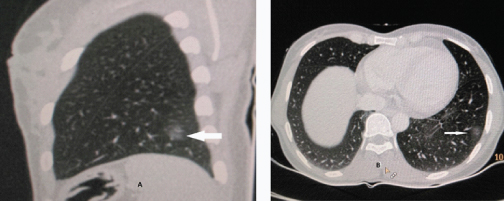

A 32-year-old female patient was admitted in pulmonary medicine ward with complaints of 20 episodes of haemoptysis since 11 months. She had no history of smoking and the tuberculosis work up by her treating physician was negative. Her clinical examination, blood picture and X-Ray chest PA view revealed no abnormality. She was referred to Department of Radiodiagnosis for HRCT Chest which revealed subtle area of ground glass haze in posterior basal segment of left lower lobe sub pleural in location [Table/Fig-1]. This HRCT was done when she was menstruating. On detailed clinical history the haemoptysis occurred during menstruation period with weakness and weight loss. Cough with expectoration of blood reoccurred every menstruation period lasting for few days. Total amount of blood expectorated as per patient’ s version was approximately 20-30 ml. She had history two normal vaginal deliveries and dilatation and curettage one year back for missed abortion. She gave no history of endometriosis. Ultrasonography of pelvis was normal. A repeat CT was done after control of haemoptysis and during non-menstruating period after 16 days of first CT. It showed complete resolution of the lesions [Table/Fig-2]. A diagnosis of thoracic endometriosis with catemenial haemoptysis was made. Bronchoscopy revealed hyperemic areas in left apicoposterior bronchus upper lobe and in right upper lobe apical segment bronchus. Bronchial washing was taken. Bronchial washing turned to be negative. Patient was put on tab Danazol 200 mg BD medical therapy, to which she responded well and suffered only one more minimal bout of haemoptysis. Monthly follow up visits were uneventful. Medication was discontinued after four months. After 8 months follow up the patient is clinically normal and had no fresh episodes of haemoptysis.

Sagittal and axial view showing subtle ground glass opacity in posterior basal segment of left lower lobe (Arrows).

HRCT thorax is non-specific and may reveal ground glass or well-defined opacities, nodular lesions and thin-wall cavities [7] but it is the modality of choice for localization of endometrial deposits in the lung and pleura. In the presence of characteristic history and clinical examination, findings HRCT are considered diagnostic of pulmonary endometriosis [8]. Pleural lesions are usually right-sided, whereas lung lesions can be on either side [2]. This is explained by the fact that the lymphatic drainage is more extensive on right side of the diaphragmatic surface so embolic implant is more likely on right side [9]. HRCT chest in our patient revealed subtle area of ground glass haze in posterior basal segment of left lower lobe. This CT was taken during her menstrual period. Subsequent CT chest taken during non-menstruating phase showed complete resolution of the lesion. Serial HRCT findings along with the patient’s typical history were diagnostic of thoracic endometriosis.